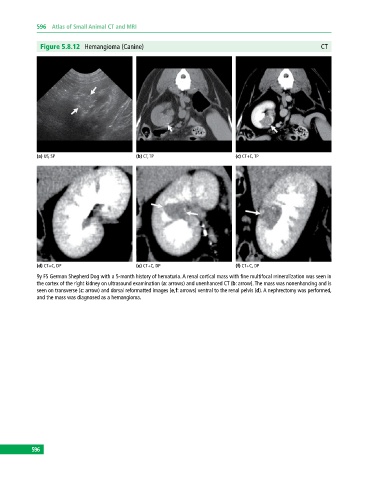

Figure 5.8.12 Hemangioma (Canine) CT

(a) US, SP (b) CT, TP (c) CT+C, TP

(d) CT+C, DP (e) CT+C, DP (f) CT+C, DP

9y FS German Shepherd Dog with a 5‐month history of hematuria. A renal cortical mass with fine multifocal mineralization was seen in

the cortex of the right kidney on ultrasound examination (a: arrows) and unenhanced CT (b: arrow). The mass was nonenhancing and is

seen on transverse (c: arrow) and dorsal reformatted images (e,f: arrows) ventral to the renal pelvis (d). A nephrectomy was performed,

and the mass was diagnosed as a hemangioma.